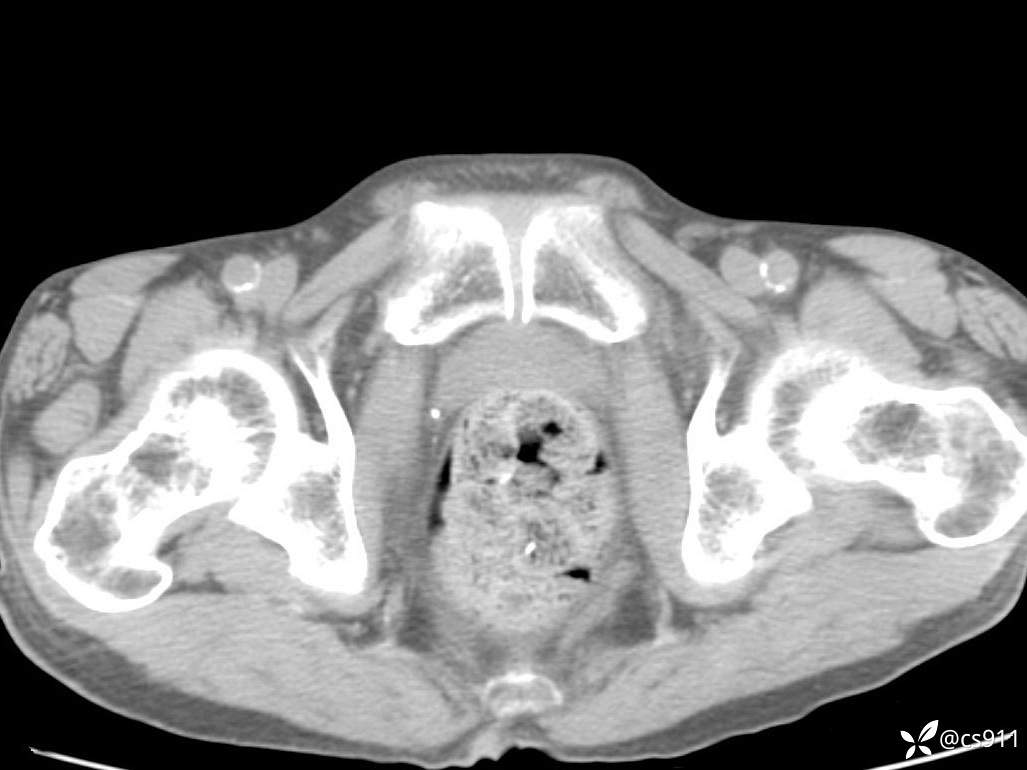

急腹症之急诊CT,原因?答案公布

男,77岁,腹痛、腹胀伴恶心呕吐1天。呕吐胃内容物,非喷射性呕吐,有咖啡色样胃内容物,诉有胃穿孔病史。查体:全腹平,下腹部压痛,全腹无反跳痛,叩诊呈浊音,移动性浊音阴性,肠鸣音减弱,1-2次/分。肛检:直肠未扪及明显肿物,可触及大量粪块。

T 36.6℃ P 80次/分 R 26次/分 BP 100/60mmHg

白细胞(WBC) H 14.55 10e9/L 4-10

红细胞(RBC) 4.58 10e12/L 4.3-5.8

中性粒细胞百分率(NEUT%) H 85.7 % 40-75

血淀粉酶(AMY) HH 1859 U/L 35-135

癌胚抗原(CEA) H 27.44 ng/ml 0-5

呕吐物 潜血试验 * 阳性 阴性

患者轮椅入室检查神志清楚, 能配合摆位和呼吸